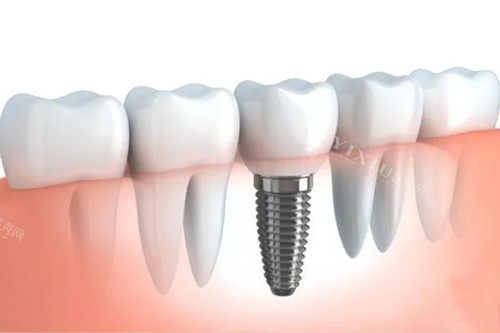

韩国丽维思亲水种植体在口腔种植领域属于中端档次的产品。这一品牌以相对合理的价格和针对东方人骨骼特点的优化设计为主要特点,在市场上占据着一定的份额。与高端品牌相比,它在品牌影响力和长期使用结果方面存在一定差距,但对于预算有限又希望获得较好结果的患者来说,是一个值得考虑的选择。

韩国丽维思亲水种植体在技术上有几个值得关注的亮点。首先,它采用了特殊的亲水表面处理技术,这项技术能够促进骨组织与种植体的结合速度,提高初期稳定性。其次,在结构设计上,通过优化螺纹结构和采用锥形连接方式,增强了种植体在口腔内的稳固性,这种设计尤其适合骨量不足或情况较为复杂的病例。从适用范围来看,这款种植体既能满足前牙区的美学修复要求,也能胜任后牙区的承重功能修复,同时对骨量不足的患者也表现出较好的适应性。